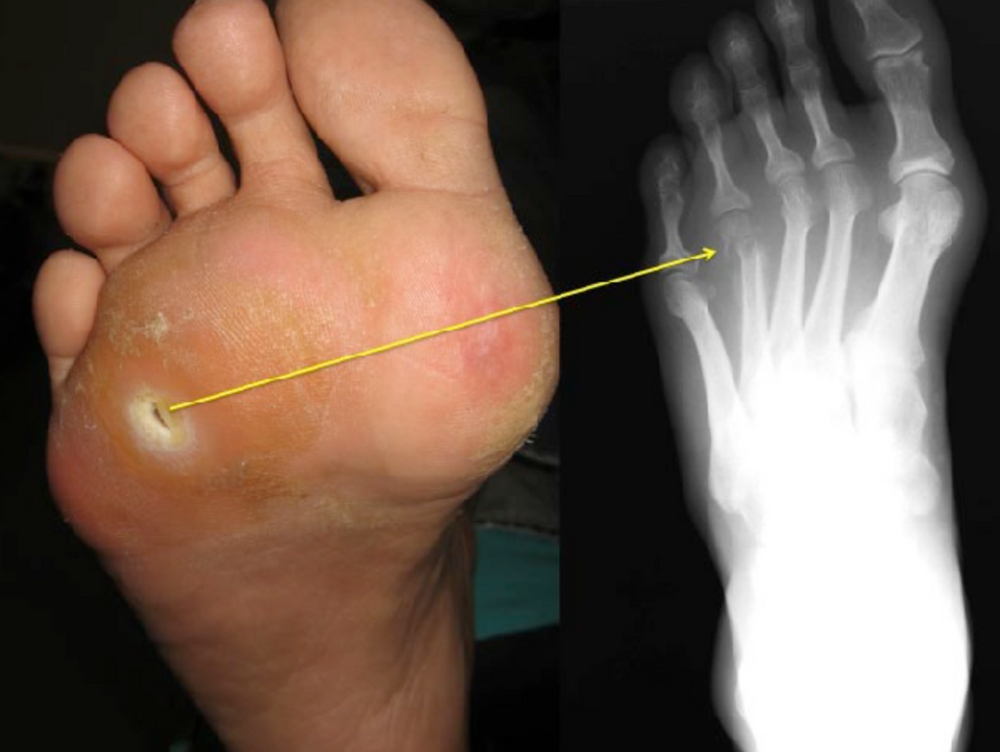

Nonsurgical treatment of diabetic foot osteomyelitis The Lancet Osteomyelitis Symptoms Reddit If you have acute osteomyelitis, you're probably going to have a fever, fatigue, cellulitis (swelling that's red and warm to the touch), drainage in your. Swelling, warmth and redness over the area of the infection; What are the symptoms of osteomyelitis? Osteomyelitis symptoms can vary depending on which type you have and which of your bones are infected. Suspect chronic. Osteomyelitis Symptoms Reddit.

Osteomyelitis X Ray Findings Osteomyelitis Symptoms Reddit Part of the bones, joints and muscles category. Osteomyelitis symptoms can vary depending on which type you have and which of your bones are infected. What are the symptoms of osteomyelitis? Symptoms of osteomyelitis vary, depending on the cause and whether it is a rapid or slow onset of infection. Hi, i was diagnosed with chronic recurrent multifocal osteomyelitis about. Osteomyelitis Symptoms Reddit.